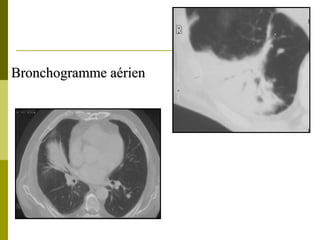

RRaaddiiooggrraapphhiiee ppuullmmoonnaaiirree

Condensation

TypiquLeS dDet …légionellose (75%)

Bronchogramme aérien

SSccaannnneerr vvss rraaddiiooggrraapphhiiee

TDM :Infiltrat bilatéral

-LSdt, apical LIG,

-pyramide basale

Syrjala CID 1998